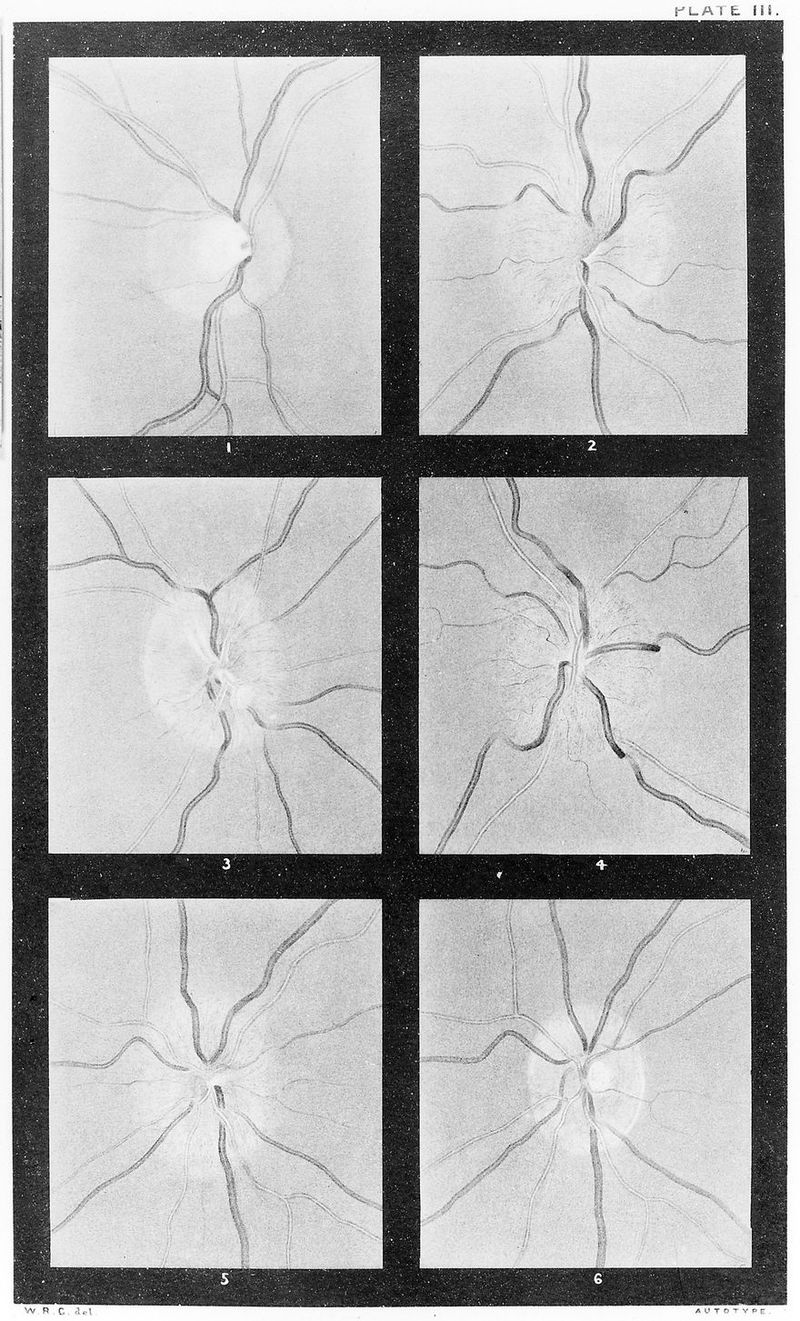

M0019102: Appearance of optic disc using an ophthalmoscope, 1879

Credit: M0019102: Appearance of optic disc using an ophthalmoscope, 1879. Source: Wellcome Collection.